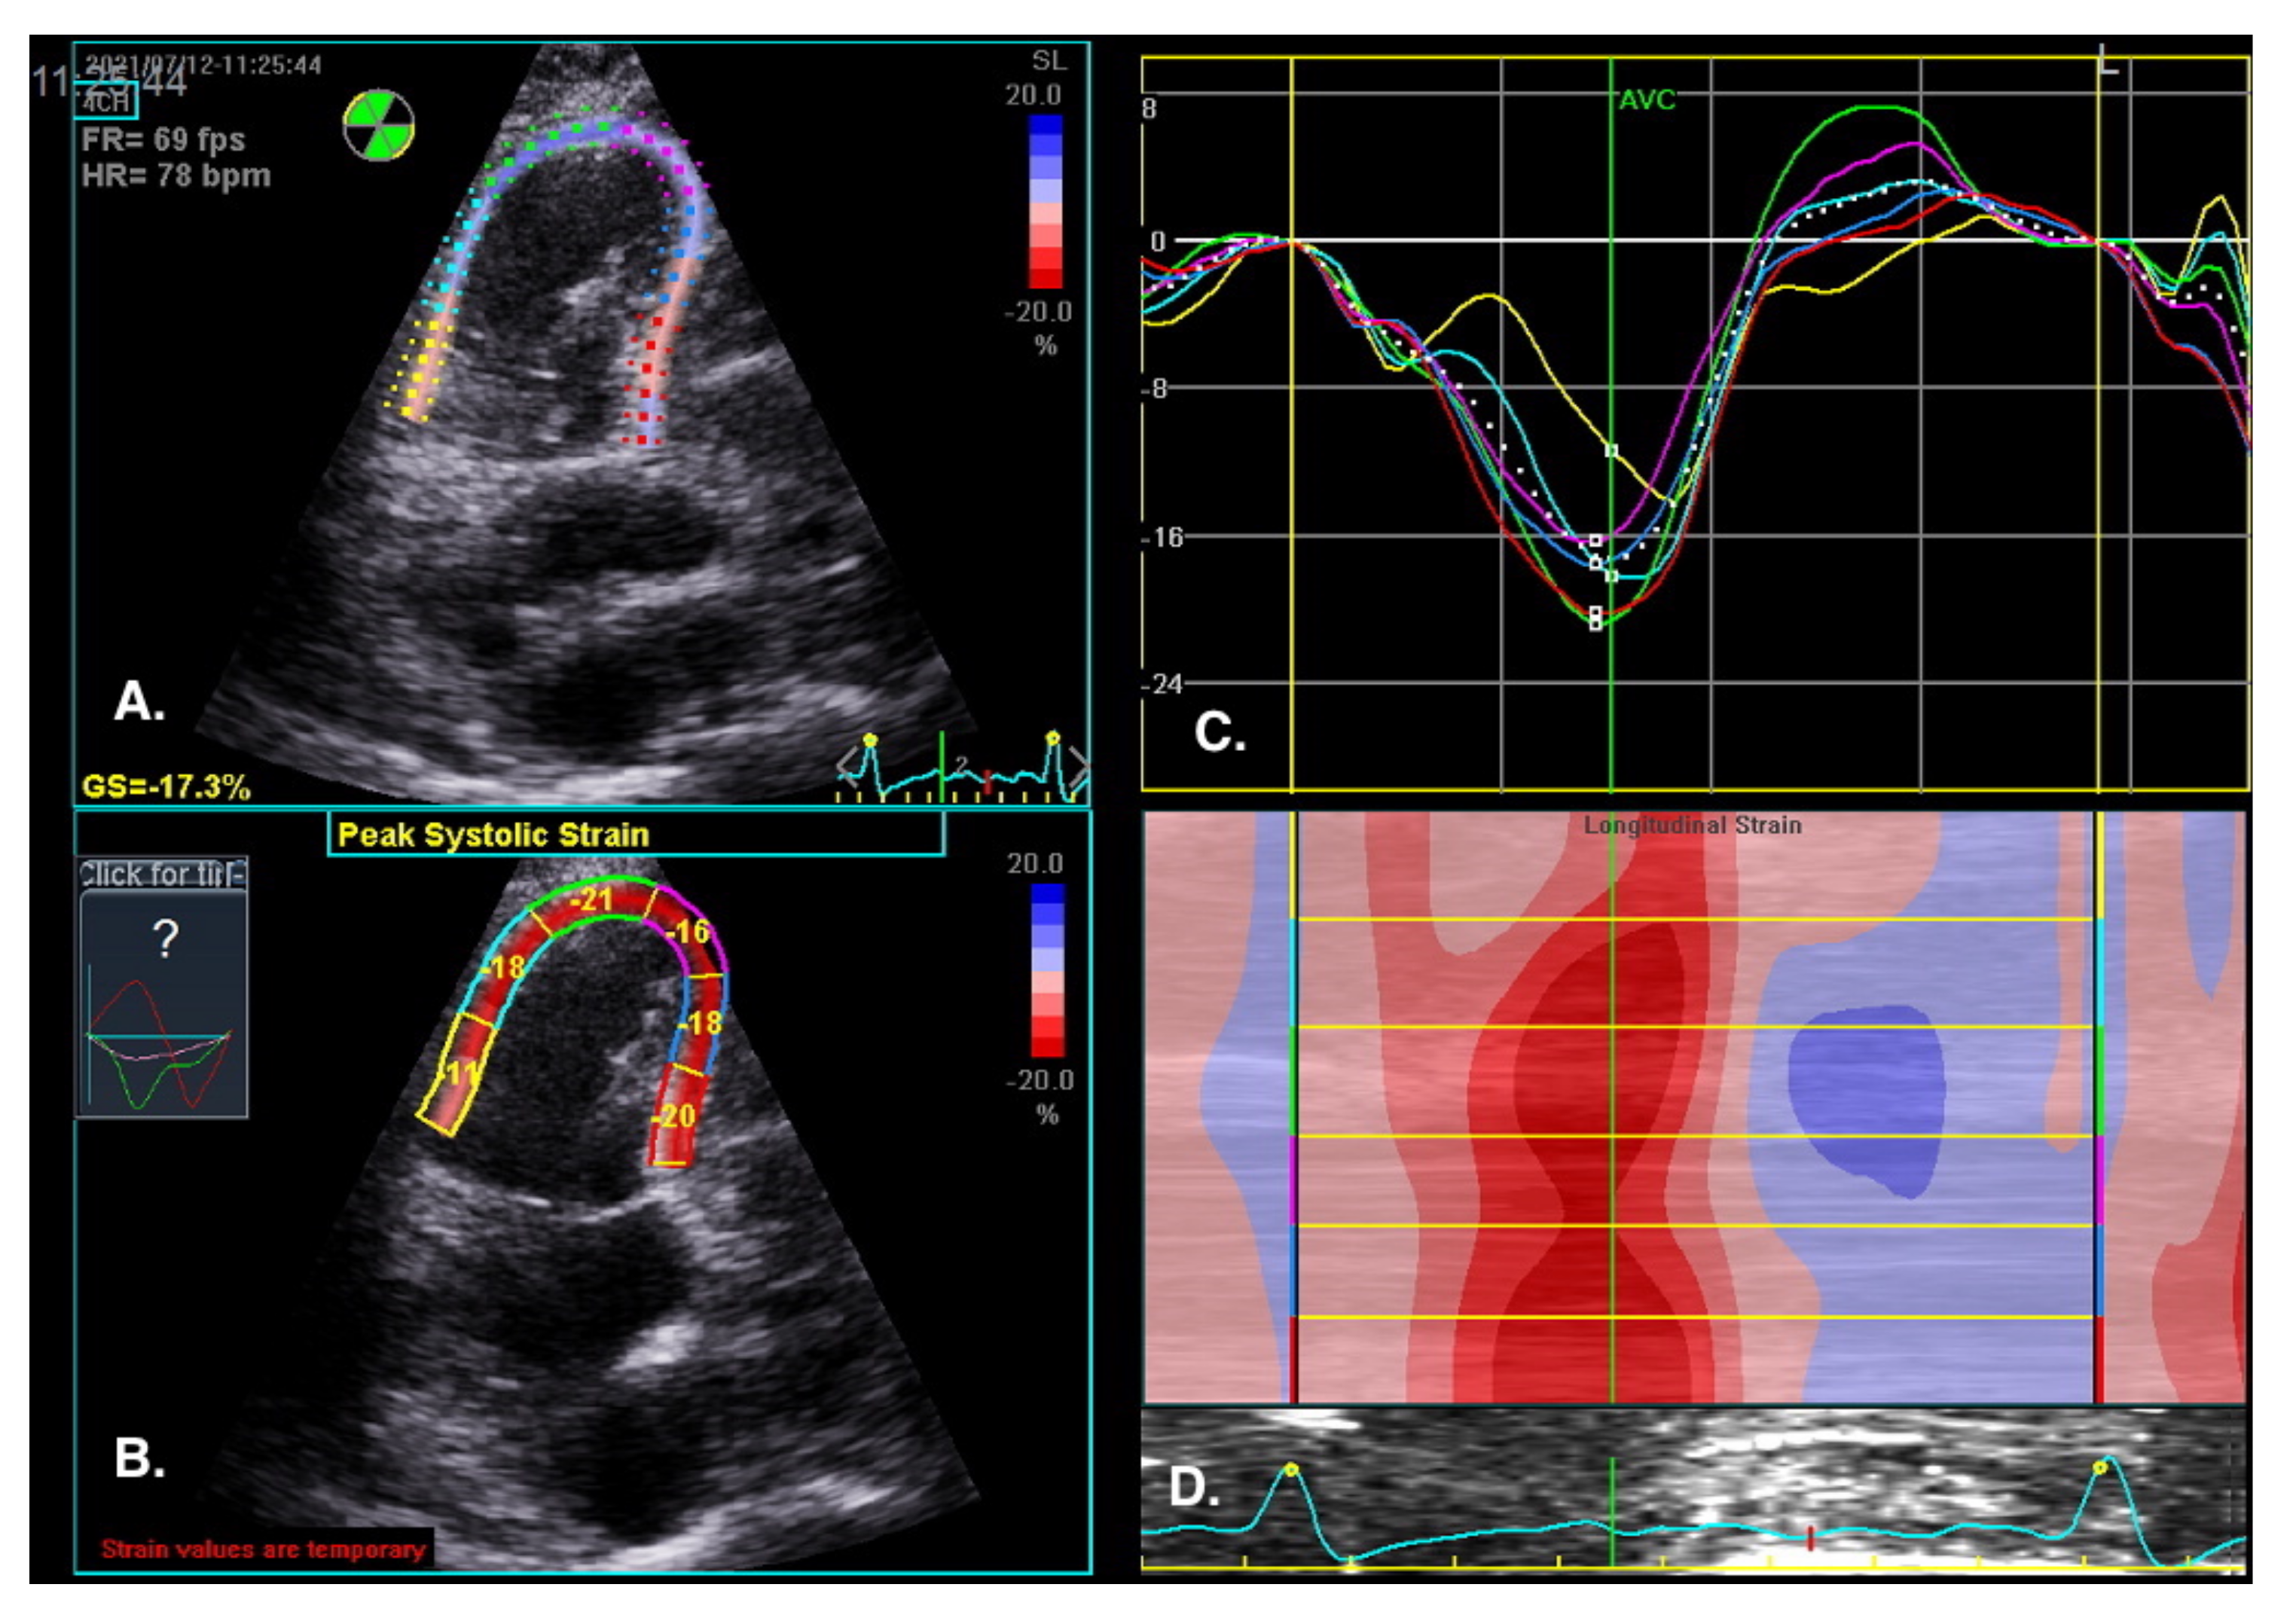

The visual assessment of myocardial contractility is very subjective and requires considerable experience from the investigator. New techniques can objectify the assessment of the segmental and global RV systolic function [59]. Myocardial strain is the percentage change in the distance between two points in the heart muscle during the cardiac cycle. In contrast, the strain rate is the rate of change in the distance between these points and is expressed in units of s−1. Initially, strain and strain rate were evaluated using TDI [60]. Currently, 2D strain and speckle tracking techniques are used, which involve automatic tracking of myocardial acoustic markers in standard echocardiographic images [61]. It allows the analysis of strain and strain rate in different directions (Figure 10). A newer and more precise technique for the assessment of strain and strain rate is three-dimensional echocardiography. This technology is currently under intensive development; however, reports of this method′s high efficacy in assessing the prognosis in patients with PAH are already available [62].

Figure 10.

RV regional myocardial contractility (longitudinal strain) assessment by speckle tracking imaging. RV-focused view, 4CH. (A) Tracked apical loop with colour coding of the RV free wall and interventricular septum myocardial segments. (B) Regional end-systolic strain. (C) Segmental strain curves and segmental strain values displayed during the cardiac cycle. Global longitudinal strain at peak strain is visualized with the global strain curve (white dotted line). (D) M-mode representation of peak systolic strain. Blue colour- myocardial lengthening, red colour- myocardial shortening.

The normal RV systolic strain values in healthy subjects amount to: RV global strain −24.5 ± 3.8 and RV free wall strain −28.5 ± 4.8 [63].

The advantage of these methods is that they offer a very precise analysis of individual myocardial segments’ function, which enables visualization of discrete abnormalities, and detection of early stages of systolic dysfunction, often impossible to detect with conventional echocardiography [64].

Sachdev et al. demonstrated that RV longitudinal peak systolic strain (−15 ± 5%) and strain rate (−0.80 ± 0.29 s) are significantly reduced in patients with PAH. Moreover, RV-free wall strain was also reduced in the study group, which was associated with a decreased 1-year survival [65]. Other studies show that right atrial strain may also have a diagnostic value in patients with PAH [66].

A: Tracked apical loop with color coding of the RV-free wall and interventricular septum myocardial segments. B: Regional end-systolic strain. C: Segmental strain curves and segmental strain values displayed during the cardiac cycle. Global longitudinal strain at peak strain is visualized with the global strain curve (white dotted line). D: M-mode representation of peak systolic strain. The normal RV systolic strain values in healthy subjects amount to an RV global strain −24.5 ± 3.8 and RV free wall strain −28.5 ± 4.8 [63].